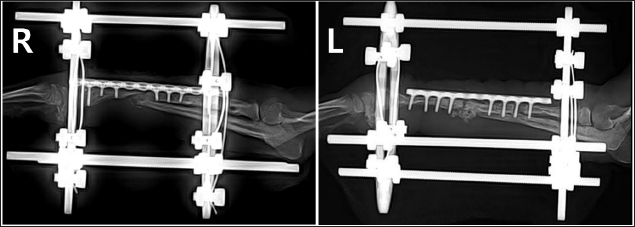

A two-step surgical plan was developed for managing the fractures. The remaining pin was removed in the first surgery and a CEF was applied for temporary fixation (Fig. 2A and B). Pins used included two 0.9 mm K-wires placed proximally and distally in a crossed manner, and one 1.2 mm olive wire placed in a single location. Anticipation of bone regeneration around areas of bone lysis near screw holes, and physical rehabilitation focused on inducing forelimb use until the second surgery. During the 6-week maintenance period of the temporary external fixation device, partial bone regeneration was observed in some areas of bone loss (Fig. 2C and D). Although forelimb ambulation remained plantigrade, there was an improvement in utilizing the limb smoothly with weight-bearing. In the second surgery, the CEF device was removed, and a surgical approach was made to apply the bone plate. The atrophied fracture sites on both sides showed no signs of bone regeneration and were partially debrided to expose the bone marrow cavities. The fracture was then fixed with a long bone plate and 1.5 mm screws. Autografts were harvested from the iliac wing and transplanted around the fracture site. This procedure was performed identically on both limbs with the fascia and skin closed in a standard manner. Additionally, CEF methods involved applying 0.9 mm K-wires, the same size as those used in the first surgery, above and below the plate on the fractured radius to provide further stability (Fig. 3).

Fig. 2. Radiographs taken immediately after the first surgery and 6 weeks postoperatively, showing the effects of temporary circular external fixation on bone remodeling. (A) Immediate postoperative view of right radius and ulna. (B) Immediate postoperative view of left radius and ulna. (C) 6-week postoperative view of right radius and ulna. (D) 6-week postoperative view of left radius and ulna.

Previous studies have highlighted challenges in using external fixation in toy-breed dogs due to their size, particularly in the radius (Hamilton and Langleyhobbs, 2005). However, based on the author’s clinical experience with successful CEF applications, this study initially applied CEF for temporary fixation to promote the reconstruction of lysed bone and stabilize surrounding soft tissue. Rehabilitation was performed to maintain joint function, promote vascularization, and enhance muscle mass until a second surgery was conducted. Although radiographic evaluation revealed no signs of union at the fracture site, the frequency of forelimb use increased after temporary fixation. Six weeks after the first surgery, radiography showed increased bone thickness and a decrease in the areas of lysis. In the second surgery, the fracture was reduced using plates and screws, and CEF was applied simultaneously for 4 weeks. During the 10 weeks of CEF application, no complications such as infections or implant loosening were observed, and it provided the necessary stability to maintain alignment and regenerate the bone.